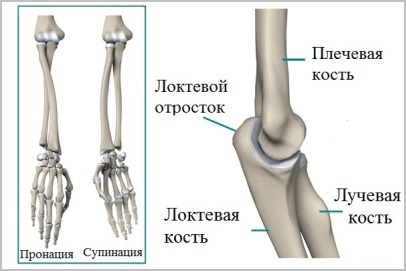

antebraț anatomie

Există două oase ale antebrațului. Cubitus și linia mai subțire, se formează axa de rotație a antebrațului. Raza se rotește în jurul ulna în antebraț în timpul mișcării.

În cazul în care oasele antebrațului sunt fuzionate cu un offset sau anatomie a oaselor nu a fost restaurat cu acuratețe după operație, rotirea razei în raport cu cotul va fi greșit. Rezultatul final va fi o limitare bruscă a mișcării în toate extremitățile.